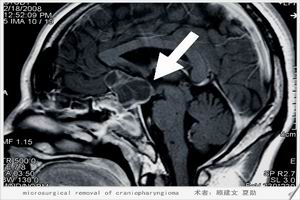

MRI檢查與CT的效果相仿,但可在橫、冠、矢3相檢查,腦脊液為更長T1及T2。

5.CT掃描及磁共振成像高分辨力的CT冠狀位掃描或磁共振成像能迅速而又無創傷地作出診斷。典型圖像示鞍窩擴大,垂體萎縮變形,被充滿與鞍上池同樣低密度的腦脊液取代。若作造影劑強化直接冠狀位CT掃描,則未見增強。重症患者垂體嚴重受壓,被推移至後下方呈薄片狀,垂體柄可深達鞍底,形成特徵性的“漏斗征”(infundibulum)。